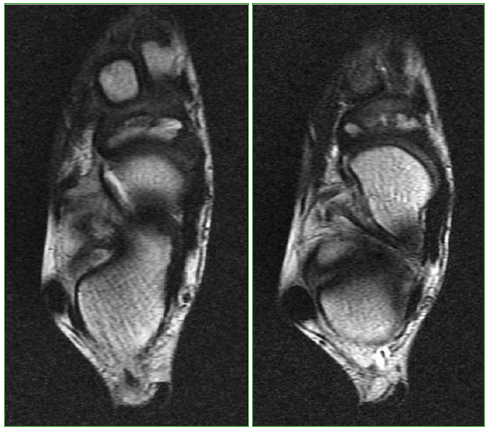

Figura 7.

Resonancia magnética, plano coronal, en secuencia T1. Se visualizan los mismos hallazgos en el pie derecho.

Figura 8.

Resonancia magnética, plano axial, secuencia T1. Se visualizan los mismos hallazgos en el pie derecho.